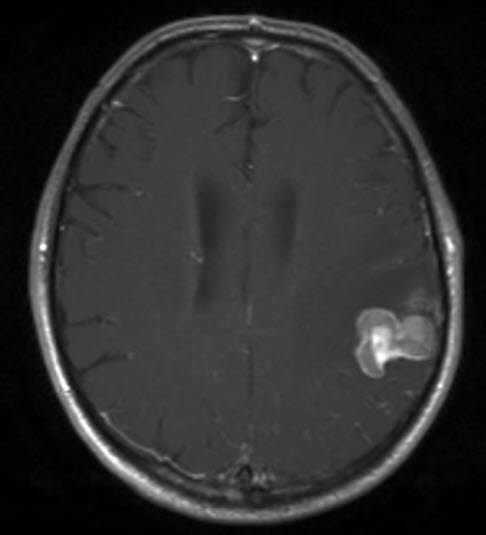

Hjernemetastase nyrekreft, aksialt snitt

Gjengitt med tillatelse av Radiologisk avdeling, Universitetssykehuset Nord-Norge